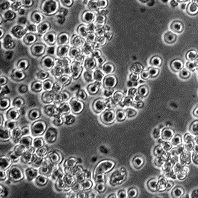

Паспорт коллекционной клеточной линииP3X63Ag8.653

Происхождение: мышь BALB/c, миелома, клон линии P3X63Ag8.

Морфология: лимфоидная

Способ культивирования: суспензионный